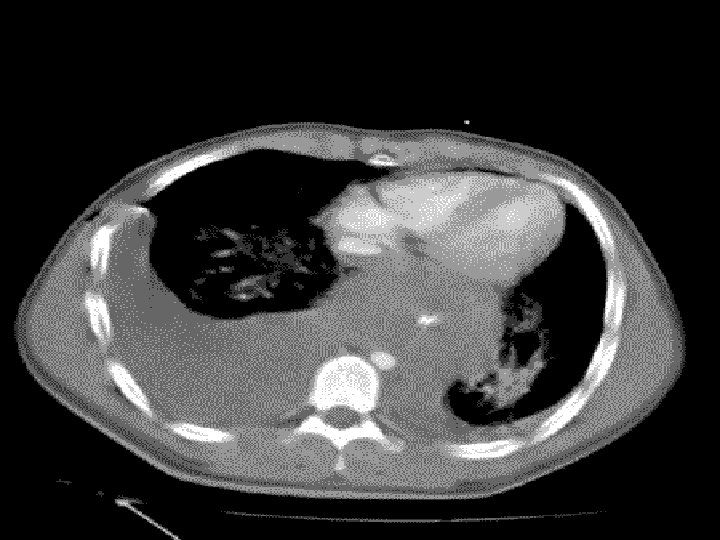

Aortic Transection v. Mechanism: - • shearing force • Direct luminal pressure against point of traction. q. Diagnosis • X-ray : widening of • mediastinum with shadow CT